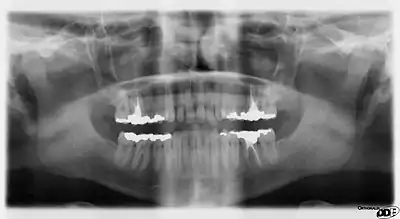

A panoramic radiograph reveals the mandible, including the heads and necks of the mandibular condyles, the coronoid processes of the mandible, as well as the nasal antrum and the maxillary sinuses.